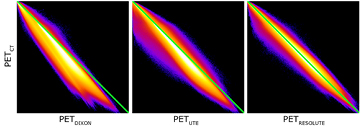

To assess the overall performance of the methods, we first computed the averaged whole brain error across all patients using (equation (3)), as well as the images of pixel-wise mean across all patients and displayed them overlaid into the ICBM template to show the distribution of errors spatially. Mean absolute error for the whole brain that disregard the direction of over- and under prediction are included for comparison. We then calculated the joint histograms between PETCT and PETDIXON, PETUTE and PETRESOLUTE, respectively, as well as the histogram of errors for each of the methods. This gave a good overall assessment of the methods.

The average error over the full brain was −0.1% (±2.8%), compared to −6.9% (±2.1%) in UTE. The mean absolute error over the full brain was 3.4% (±1.6%), compared to 8.2% (±1.9%) in UTE. The averaged %-difference image from PETCT to PETDIXON, PETUTE and PETRESOLUTE, respectively, is shown in three orientations (figure 6). Notice the error of 10–15% in UTE near the cortex (figure 6(B)). This error is reduced to less than 1% when using RESOLUTE. The results for the averaged joint histograms are shown in figure 7. The values in PETRESOLUTE are closer to PETCT than PETUTE, which is supported by the r2 scores of 0.66 for Dixon, 0.78 for UTE and 0.92 for RESOLUTE. The systematic underestimation compared to PETCT when using Dixon and UTE is significantly reduced when RESOLUTE is applied for MR-AC. A histogram of errors can be seen in supplementary figure 1 (stacks.iop.org/PMB/60/8047/mmedia). We saw an improvement of our method over UTE and Dixon, as the number of voxels greater than ±5% was significantly reduced and the number of voxels around 0% error was increased. The systematic negative bias observed in UTE and DIXON was also considerably reduced.

Standard image High-resolution imageFigure 7. Summed joint histograms of PET values in the brain for all patients. r2 = 0.66/0.78/0.92 for PETDIXON/PETUTE/PETRESOLUTE.